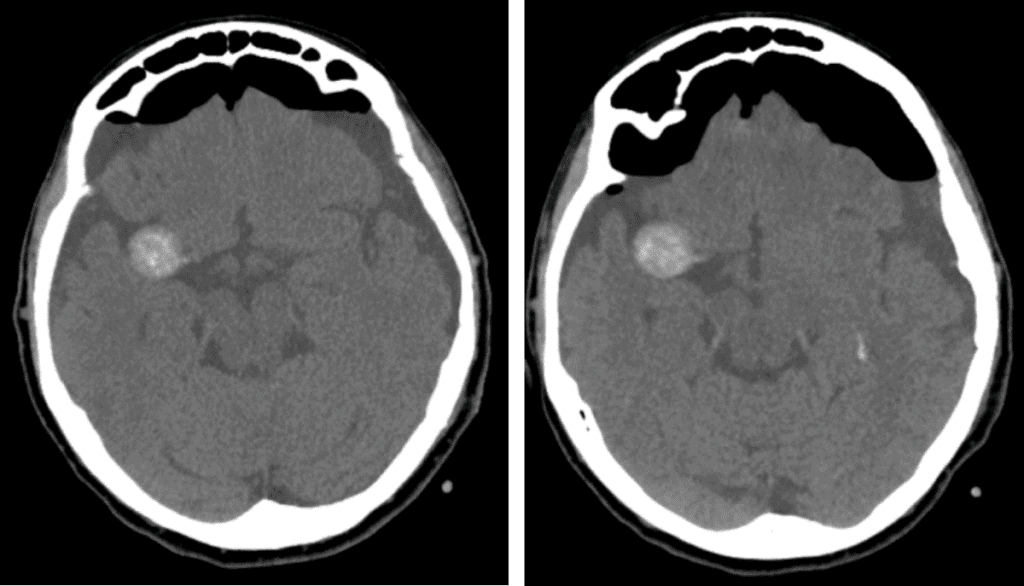

Tension Pneumocephalus

a ct scan of a tension pneumocephalus

Note the progressive compression of the frontal lobes by air with widening of interhemispheric spaces.